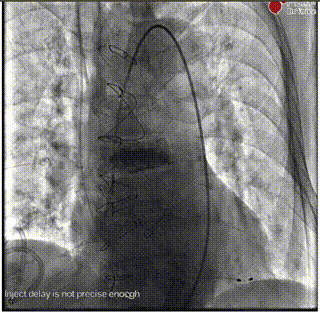

导丝跨瓣

交换猪尾

输送系统过弓

释放初期预释放

释放到50%回收

快速起搏下释放到80%

释放前造影确定位置和深度

完全释放

最后造影

术后超声

闭合血管入路,完成手术。本例难点在于SAVR术后结构性瓣膜衰败导致主动脉瓣反流,原外科瓣膜未见钙化,术前经充分沟通,确定植入深度于瓣架第一节点与第二节点间,保证瓣架底部在外科瓣膜环上具有足够锚定力。术中,瓣架完全释放前小弯侧深度稍大于大弯侧,微量PVL,在最终时提示术者对递送系统轻微施加推力,释放后两侧深度达到平衡,PVL消失,平均压差2mmHg,舒张压即刻恢复正常。